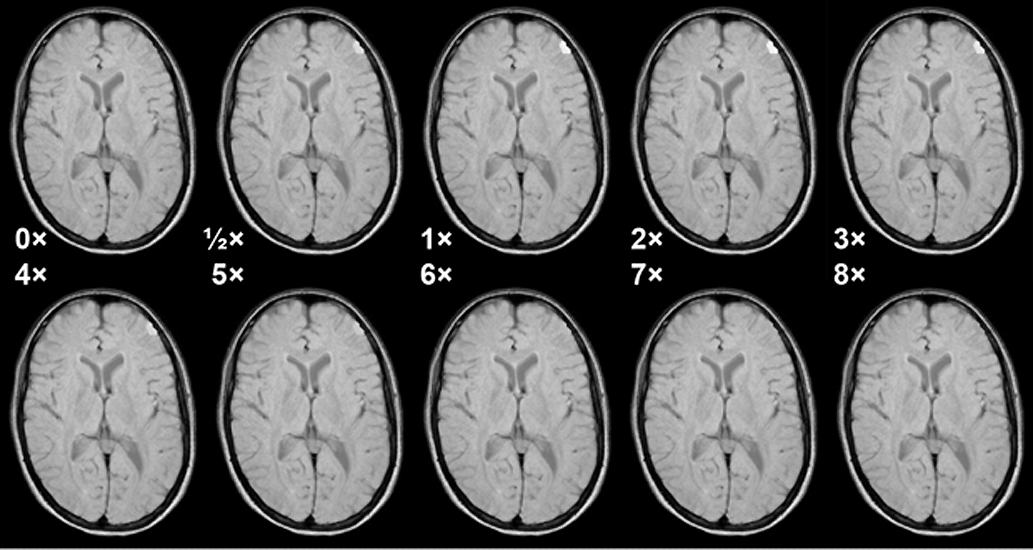

Figura 13-07:

Simulation of the influence of different tissue concentrations of Gd-based ECF space agents and mag­ne­tic field strength upon contrast in a glioblastoma. Strongly T1-weighted SE sequence, not field ad­just­ed.

Red curve = half dose; yellow = regular dose of 0.1 mmol/kg body weight; light blue = double dose; green = octuple dose.

The curves in Figure 13-07 correspond to the contrast between a glioblastoma and white matter af­ter enhancement. Before enhancement the contrast between glioblastoma and white matter is negative (the tumor is dark; its contrast behavior curve is below ½ dose but is not depicted in this figure) [⇒ Rinck 1999].

Only the regular (yellow) and double (light blue) doses give rise to sufficient con­trast at all fields. Increasing them is counterproductive (8x). Figure 13-08 shows this behavior in a meningioma.

Figura 13-08:

Simulation of the influence of different doses of a Gd-based ECF-space agent in a meningioma at 1.5 Tesla. Medium T1-weighted SE sequence. Note that at higher doses the T1 en­han­ce­ment ef­fect of the agent vanishes because T2 takes over. Best enhancement is seen at the re­com­mend­ed dose and double the recommended dose.

Simulation software: MR Image Expert®